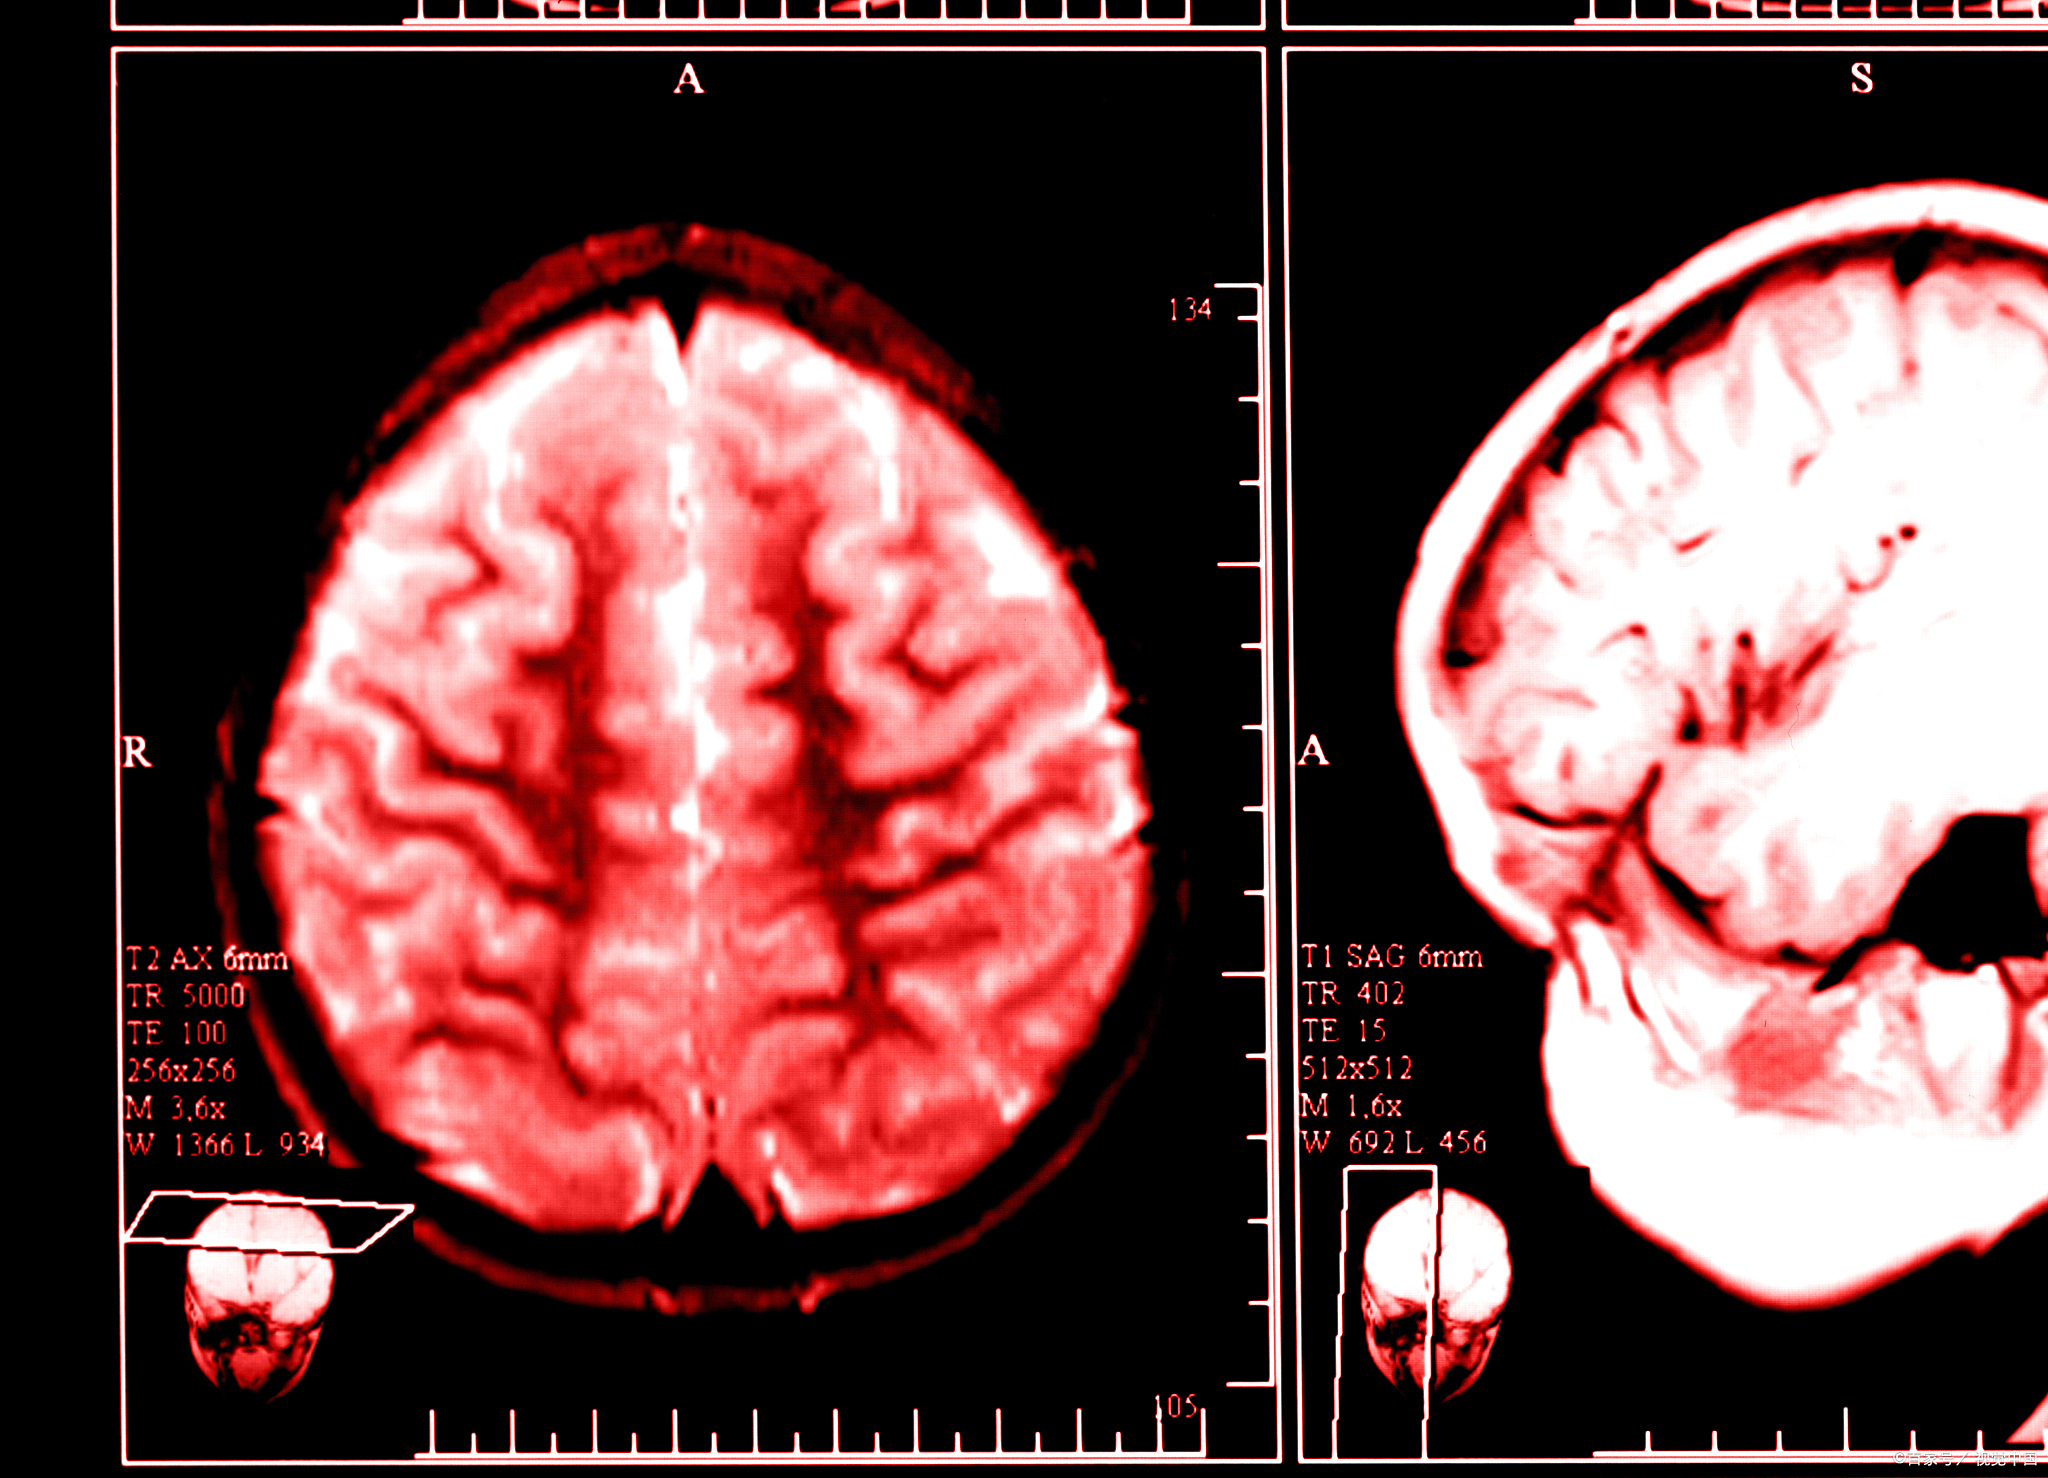

临床医生都认为只有ct才能诊断少量蛛网膜出血,殊不知mri

图片尺寸1080x1271